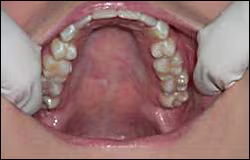

Incisive papilla – protuberance of soft tissue lingual to the maxillary central incisors which covers the incisive foramen and normally appears redder than the surrounding tissues (Figure 28)

Raphe – slightly elevated line extending from the incisive papilla to the soft palate (Figure 28)

Rugae – corrugated ridges radiating laterally from the raphe (Figure 28)

Figure 28. Normal structures of the anterior hard palate.